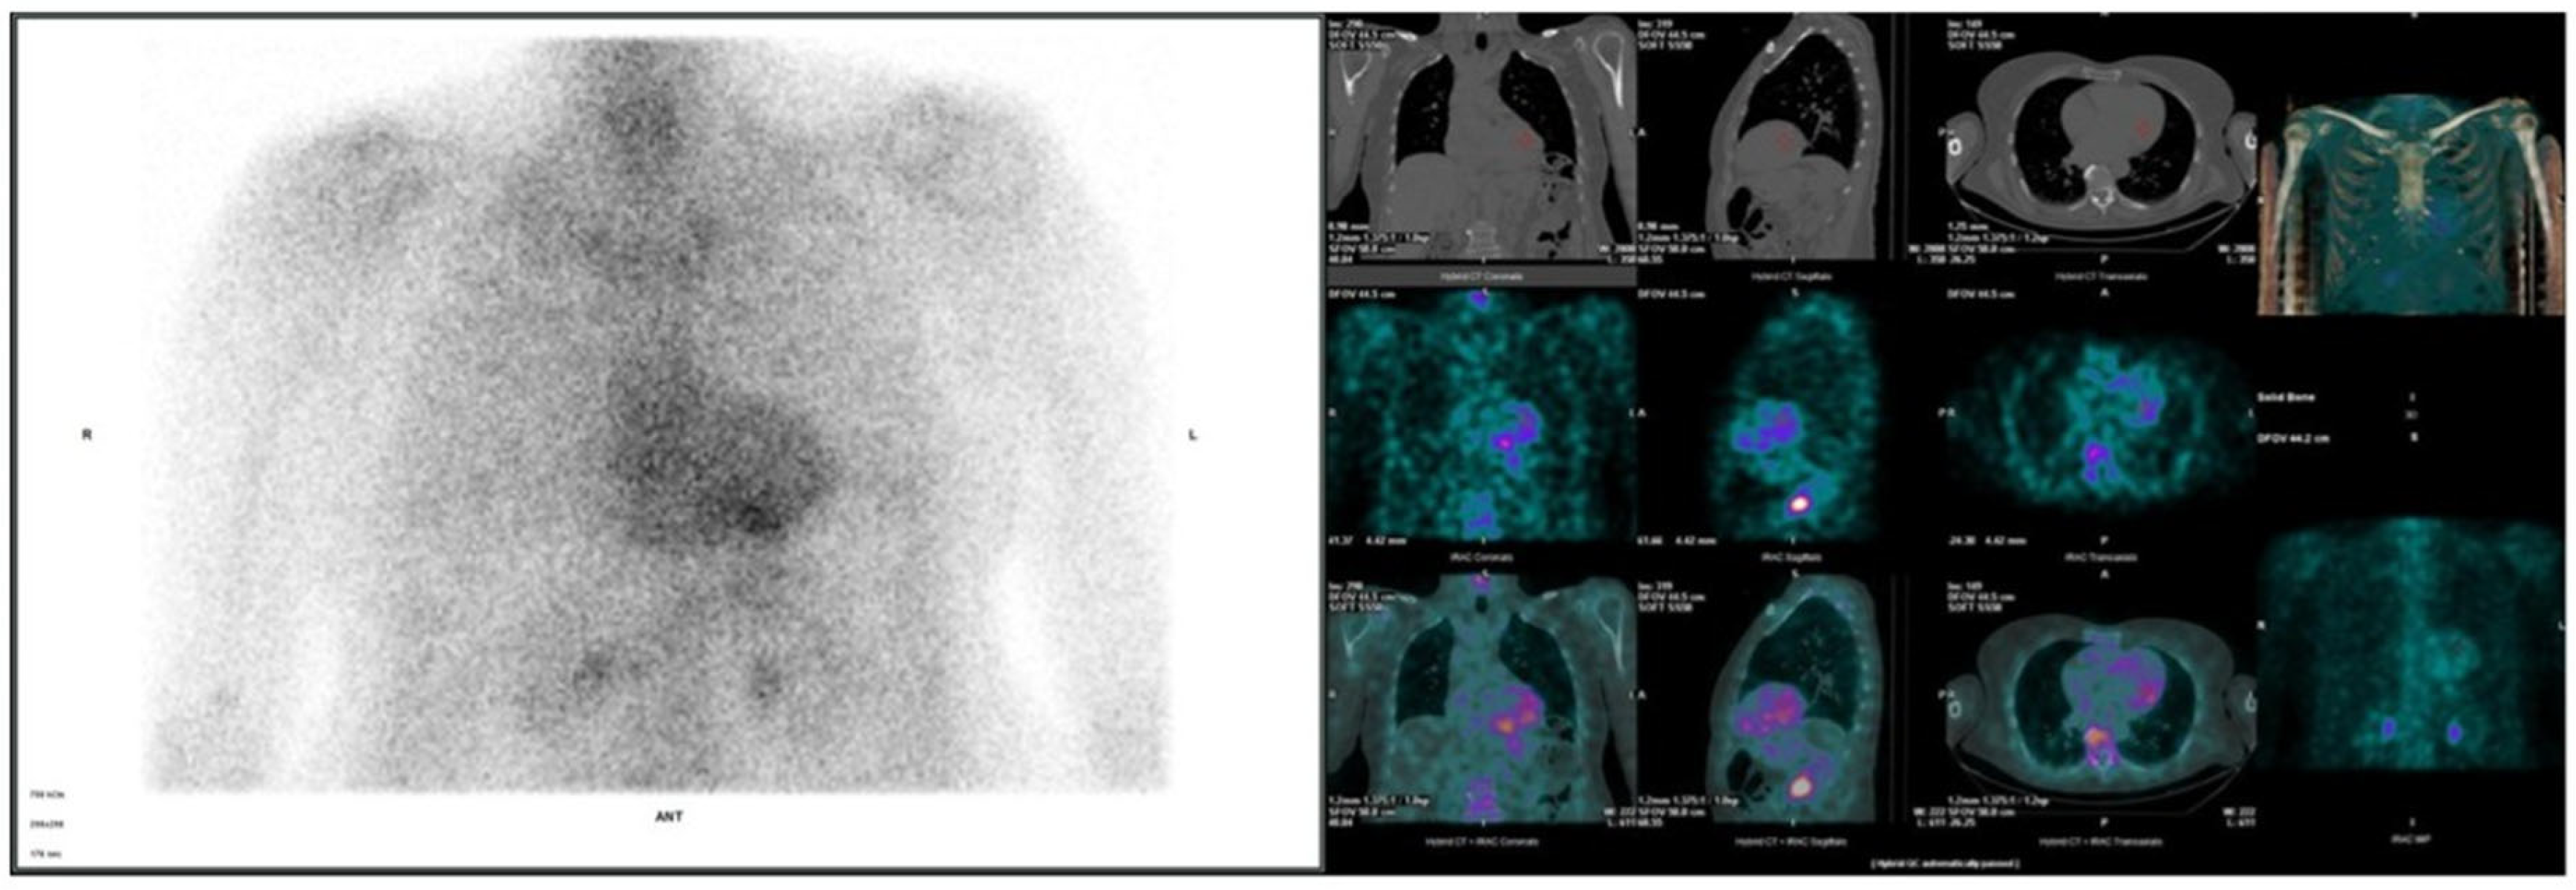

3.2. Cardiac Evaluation